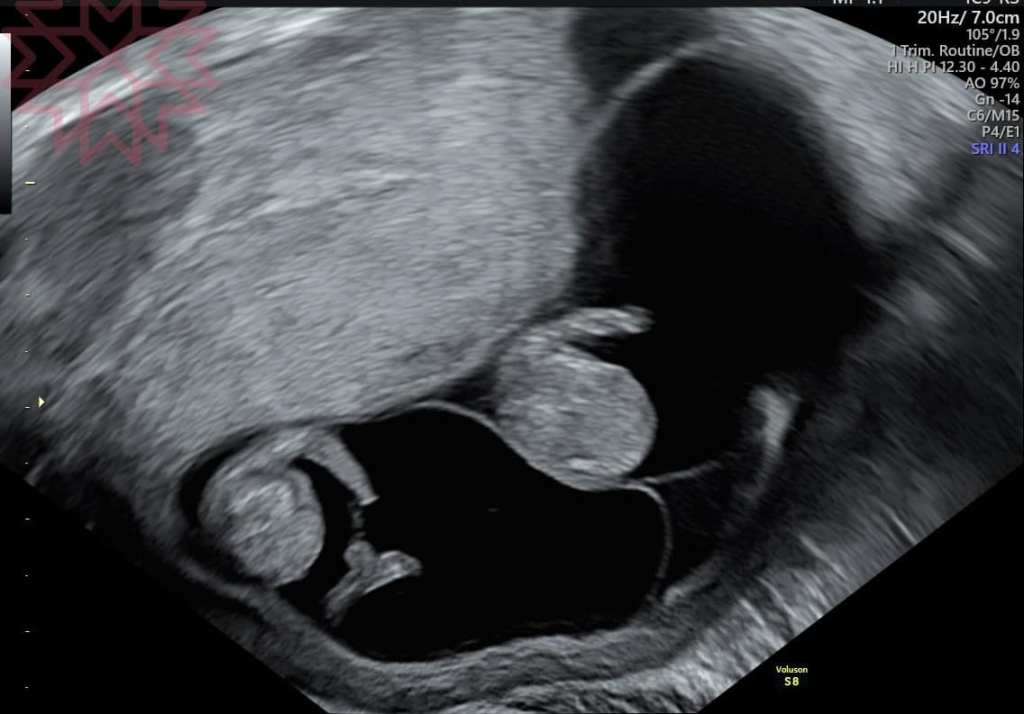

直接看圖

只要專業的醫師大概在這時候都可以知道哪一個是單絨毛膜雙羊膜哪一個是雙羊膜雙絨毛膜

1

雙絨毛膜雙羊膜(DCDA)雙胞胎

同卵跟異卵都有可能

每個胎兒都有自己獨立的胎盤跟房間各自玩各自的

這種追蹤的重點就在於胎兒的發育生長曲線跟早產的風險

其他跟單胞胎差不多

對我們產科醫師來說是相對單純的

對了

隨便挑三張

抽考一下

大家看得出來這裡面分別有幾個羊膜幾個絨毛膜嗎?

答案之後公佈